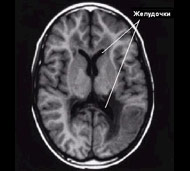

Консистенция головного мозга напоминает желе, которое, как бы, плавает в черепе со спинномозговой жидкостью. Эта жидкость также заполняет большие полые структуры, которые называются желудочками, и которые расположены в глубине головного мозга.

Спинномозговая жидкость проходит через желудочки как по взаимосвязанным сосудам и каналам. Затем жидкость попадает в закрытые пространства, расположенные между головным мозгом и черепом, где она поглощается кровотоком.

Сбалансированная выработка, циркуляция и поглощение спинномозговой жидкости имеют важное значение для поддержания нормального давления в черепе. Гидроцефалия развивается тогда, когда отток спинномозговой жидкости нарушен – например, при суженном канале между желудочками или при нарушении абсорбции жидкости организмом.